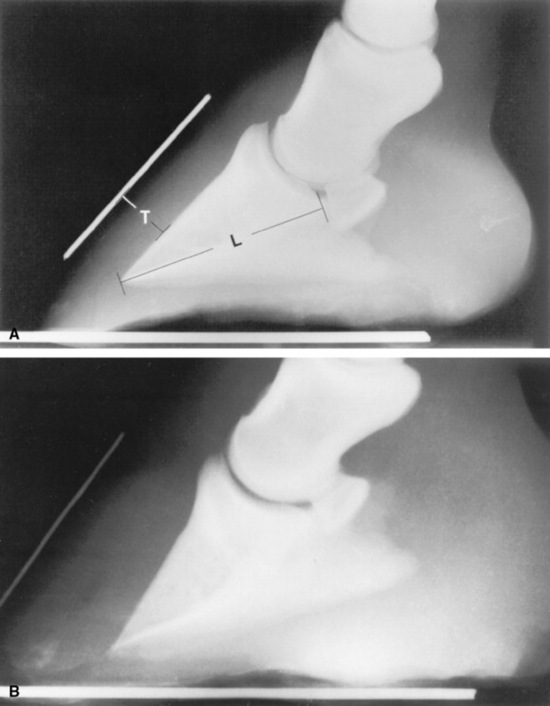

Radiographic examinations should be performed on the affected digits of horses suspected to be developing laminitis. The initial examinations should include lateromedial and 65-degree dorsoproximal-palmarodistal projections. These views should be taken to assess the appearance of the distal phalanx, the soft tissues of the hoof wall and corium, and their relationship. Lateromedial examinations are periodically repeated to check the progression of the disease. Radiographic signs of laminitis include ventral displacement of the extensor process with respect to the coronary groove of the hoof wall, increased distance between the dorsal cortex of the distal phalanx and the surface of the hoof wall, and ventral rotation of the tip of the distal phalanx. Linear radiolucencies are noted interior to the hoof wall in cases where the corium has separated from the epidermal laminae. Increasing degrees of rotation of the distal phalanx and increases in the distance between the dorsal surface of the distal phalanx and the hoof wall indicate progression of the disease (Fig. 38-30).

Fig. 38-30 A, Lateromedial radiograph of a normal digit. Two radiopaque markers can be seen. One has been placed on the block below the foot to mark the bearing surface of the wall, and the other marker identifies the location of the dorsal surface of the hoof wall. Notice that the dorsal surface of the hoof wall and the dorsal cortex of the distal phalanx are parallel, and that the distance between them, the soft tissue thickness (T), is approximately 25% of the distance from the tip of the distal phalanx to the articulation of the distal phalanx and the navicular bone, that is, the length of the distal phalanx (L). B, Lateromedial radiograph of a digit from a horse with severe laminitis. The distal phalanx has dropped ventrally without rotating. This phenomenon is seen in some horses with laminitis. The most consistent radiographic manifestation in such cases is an increased distance between the dorsal cortex of the distal phalanx and the dorsal surface of the hoof wall. The soft tissue thickness, as measured between the dorsal cortex and the dorsal surface of the hoof wall, in this case is 45% the length of the distal phalanx. The soft tissue thickness is normally less than 28% of the distal phalanx length for thoroughbred racehorses. C, Lateromedial radiograph of a digit from a horse with severe laminitis. Note the linear radiolucency dorsal to the distal phalanx (arrowhead). This lucency indicates a separation between the corium and primary epidermal laminae and marks the inner aspect of the hoof wall (arrows). The dorsal cortex of the distal phalanx is rotated approximately 14 degrees with respect to the inner surface of the hoof wall. Note that the dorsal and inner surfaces of the hoof wall are not parallel. This is the result of rasping along the distal portion of the dorsal surface of the hoof wall. The soft tissue thickness in this case is greatly increased to almost 42% of the distal phalanx length.

Because variations in technique affect subsequent radiographic distance and angle measurements, it is essential to standardize the radiographic procedure to detect small changes between examinations. For the lateromedial radiograph, the foot is cleaned and placed on a wooden block approximately 3 inches (7.5 cm) thick. A radiopaque marker can be embedded in the dorsal surface of the block and along the dorsal surface of the hoof wall to aid in determining the amount of rotation of the distal phalanx. However, marking the surface of the dorsal hoof wall is generally not necessary when digital radiographs are available. A small section of metal wire or a groove can be placed in the proximodorsal hoof wall as a reference for measuring vertical displacement of the distal phalanx in repeated radiographs, and a thumbtack is often useful in marking the apex of the frog for radiographic and anatomic correlation before therapeutic shoeing.

The radiographic beam should be perpendicular to a sagittal plane through the digit and should be centered midway between the toe and heels, about 1 inch (2 to 3 cm) above the bearing surface of the wall. The radiographic cassette should be parallel to the sagittal plane through the digit and should be placed as close to the foot as possible. Using a consistent technique and performing the examination in a standardized manner permit straight lateral radiographs to be produced and allow accurate quantification of radiographic parameters so that subtle changes may be identified early.

One of the earliest and most reliable radiographic signs of laminar deformity is an increase in distance between the dorsal surface of the hoof wall and the dorsal cortex of the distal phalanx. When the laminar suspending mechanism fails, weight-bearing forces cause the distal phalanx to displace distally or rotate away from the dorsal hoof wall, and the increased distance between the structures can be quantitated radiographically. Increased distance between the dorsal hoof surface and the dorsal cortex of the distal phalanx was significantly associated with increased laminar deformity during laminitis.221

A laminar index measurement has been developed to reduce the need to account for differences in radiographic magnification when comparing radiographs from different hospitals, from different breeds, or from different sizes of horses. It is useful to calculate the laminar index adjacent to the proximal and distal aspects of the dorsal cortex of the distal phalanx. The proximal laminar measurement is taken as the shortest distance between the linear portion of the dorsal cortex of the distal phalanx and the dorsal surface of the hoof wall immediately distal to the extensor process of the distal phalanx; the distal laminar measurement is taken in the same way, 5 to 6 mm proximal to the tip of the distal phalanx (see Fig. 38-30). The proximal and distal measurements are used to produce proximal and distal laminar indices by expressing them as a proportion of the length of the palmar cortex of the distal phalanx, as measured from the tip of the distal phalanx to its articulation with the navicular bone. The palmar cortex measurement serves as an index of foot size, and if the proximal or distal measurements spanning the laminae are increased in relation to the length of the palmar cortex, laminar deformity has occurred. Both the proximal and the distal laminar index measurements should be less than 30% of the palmar cortex length. The index measurements ranged between 20% and 28% for nonlame racing thoroughbreds221,233 and were greater than 30% in horses with laminitis,234 ranging up to 50% to 55% in those with severe laminar deformity.221 If the proximal and distal laminar indices are almost equal and both are greater than 30%, the distal phalanx has sunk in relation to the hoof capsule, without rotation (see Fig. 38-30). When both indices are greater than 30% and the distal index is greater than the proximal index, sinking and rotation of the distal phalanx have both occurred. Sinking generally indicates that laminar degeneration involves more than the dorsal wall laminae and carries a worse prognosis than for horses with rotation alone.